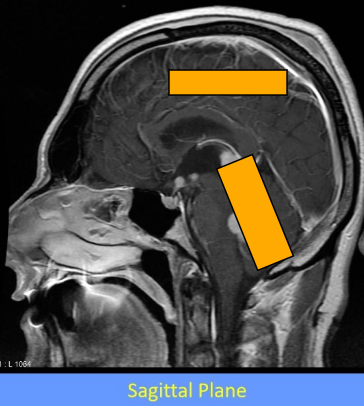

How is the cranial vault divided into compartments?

-divided into 2 continuous compartments by inward folds of the meningeal layer of dura mater

What is the tentorium cerebelli and what does it do

tent shaped fold of dura mater

divides the intracranial cavity into supratentorial and infratentorial compartments

What divides the supratentorial compartment

divided by the falx cerebri into the left and right supratentorial space which can communicate with each other and with the infratentorial space

Label this image